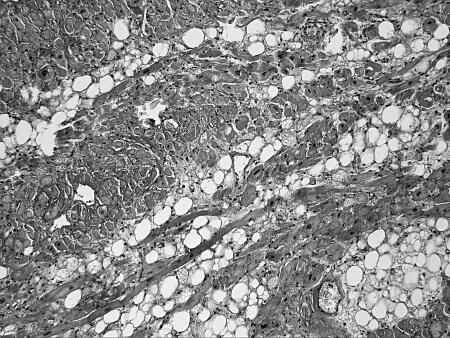

Что же общего среди всех этих состояний и что определяет их патогенетическую взаимосвязь с ФП? Очевиден механизм нарушения электрических процессов в результате ремоделирования миокарда. Данные патологоанатомических исследований подтверждают это. Так, при гистологическом исследовании ткани предсердий умерших пациентов с ФП часто выявлялись следующие изменения (см. рис. 5):

очаговый и диффузный фиброз, эндомиокардиальный фиброз, крупные разрастания зрелой волокнистой соединительной ткани по ходу межмышечных пространств и в периваскулярных пространствах (см. рис. 5 в г);

в)

г)

Рисунок 5.Гистологические изменения предсердий при ФП